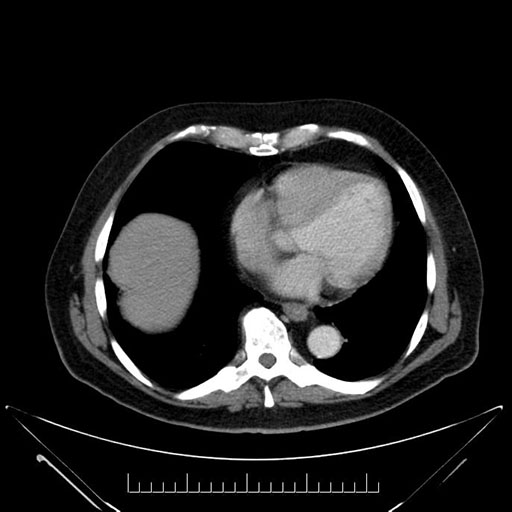

Axial - stented